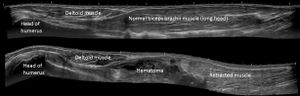

Panoramic ultrasonography

Panoramic ultrasonography of a proximal biceps tendon rupture. Top image shows the contralateral normal side, and lower image shows a retracted muscle, with a hematoma filling out the proximal space.